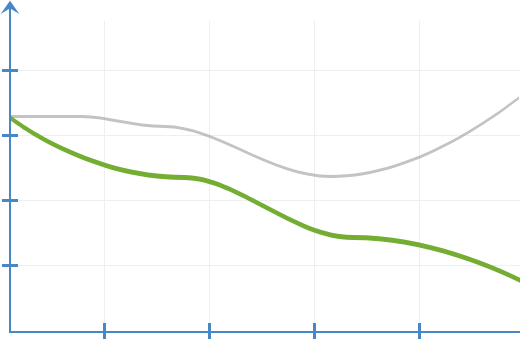

Dinamika

upalnih reakcija

bez upotrebe kapi ProDrops

sa kapima ProDrops